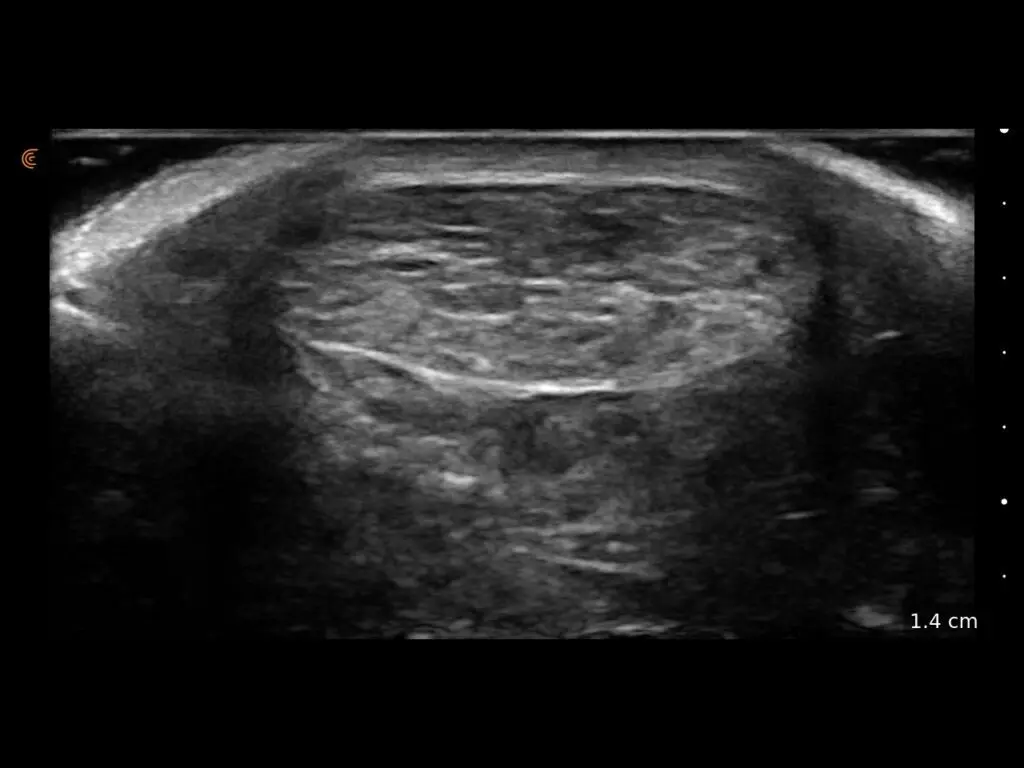

ProbeFix Dynamic is a new device that enables high-quality ultrasound measurements during dynamic exercise by keeping an ultrasound probe in place, allowing for muscle monitoring during intense movement and creating new research possibilities in muscle imaging.